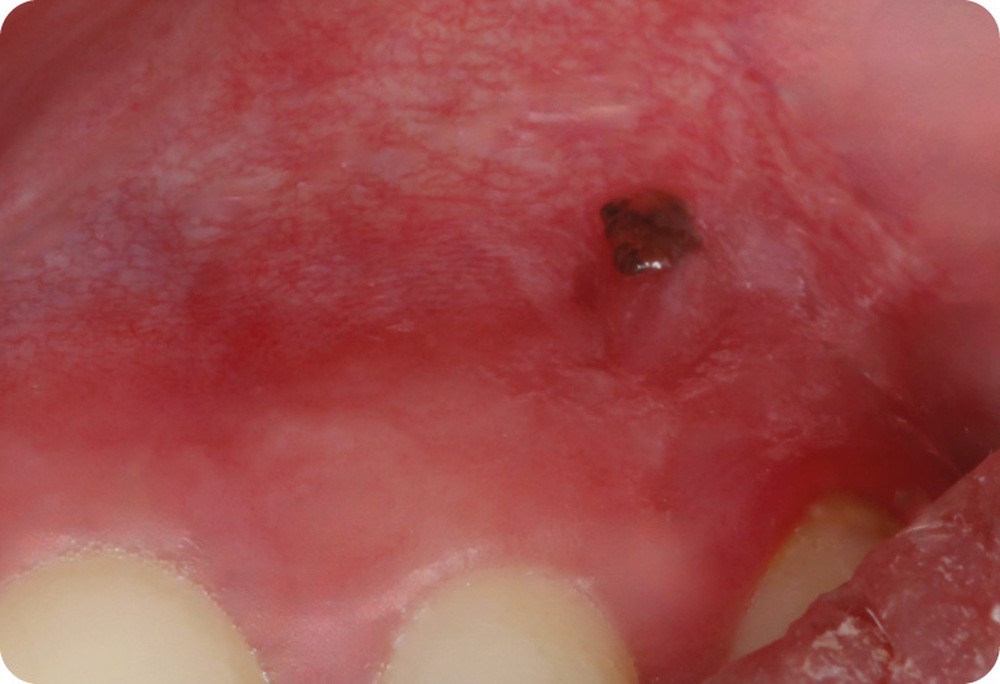

Patiente de 44 ans venue consulter sur les conseils de son dentiste traitant après la découverte, 15 jours plus tôt, d’une macule noirâtre sur la gencive.

Lors de sa dernière consultation chez son dentiste, ce dernier a découvert une macule pigmentée sur la muqueuse alvéolaire, à hauteur de 22-23. Cette lésion n’existait pas lors de la consultation précédente, un an auparavant.

La lésion était constituée par une macule noirâtre, plane, bien limitée, arrondie, de 2 mm de diamètre, siégeant sur la muqueuse alvéolaire, à la verticale de la papille interdentaire 22-23. La macule présentait un aspect tacheté associant des zones de différentes couleurs allant du noir foncé jusqu’au grisé. Il n’y avait pas d’autres lésions muqueuses, mais la patiente, bien que d’origine ibérique, présentait une peau claire avec de nombreux nævi.